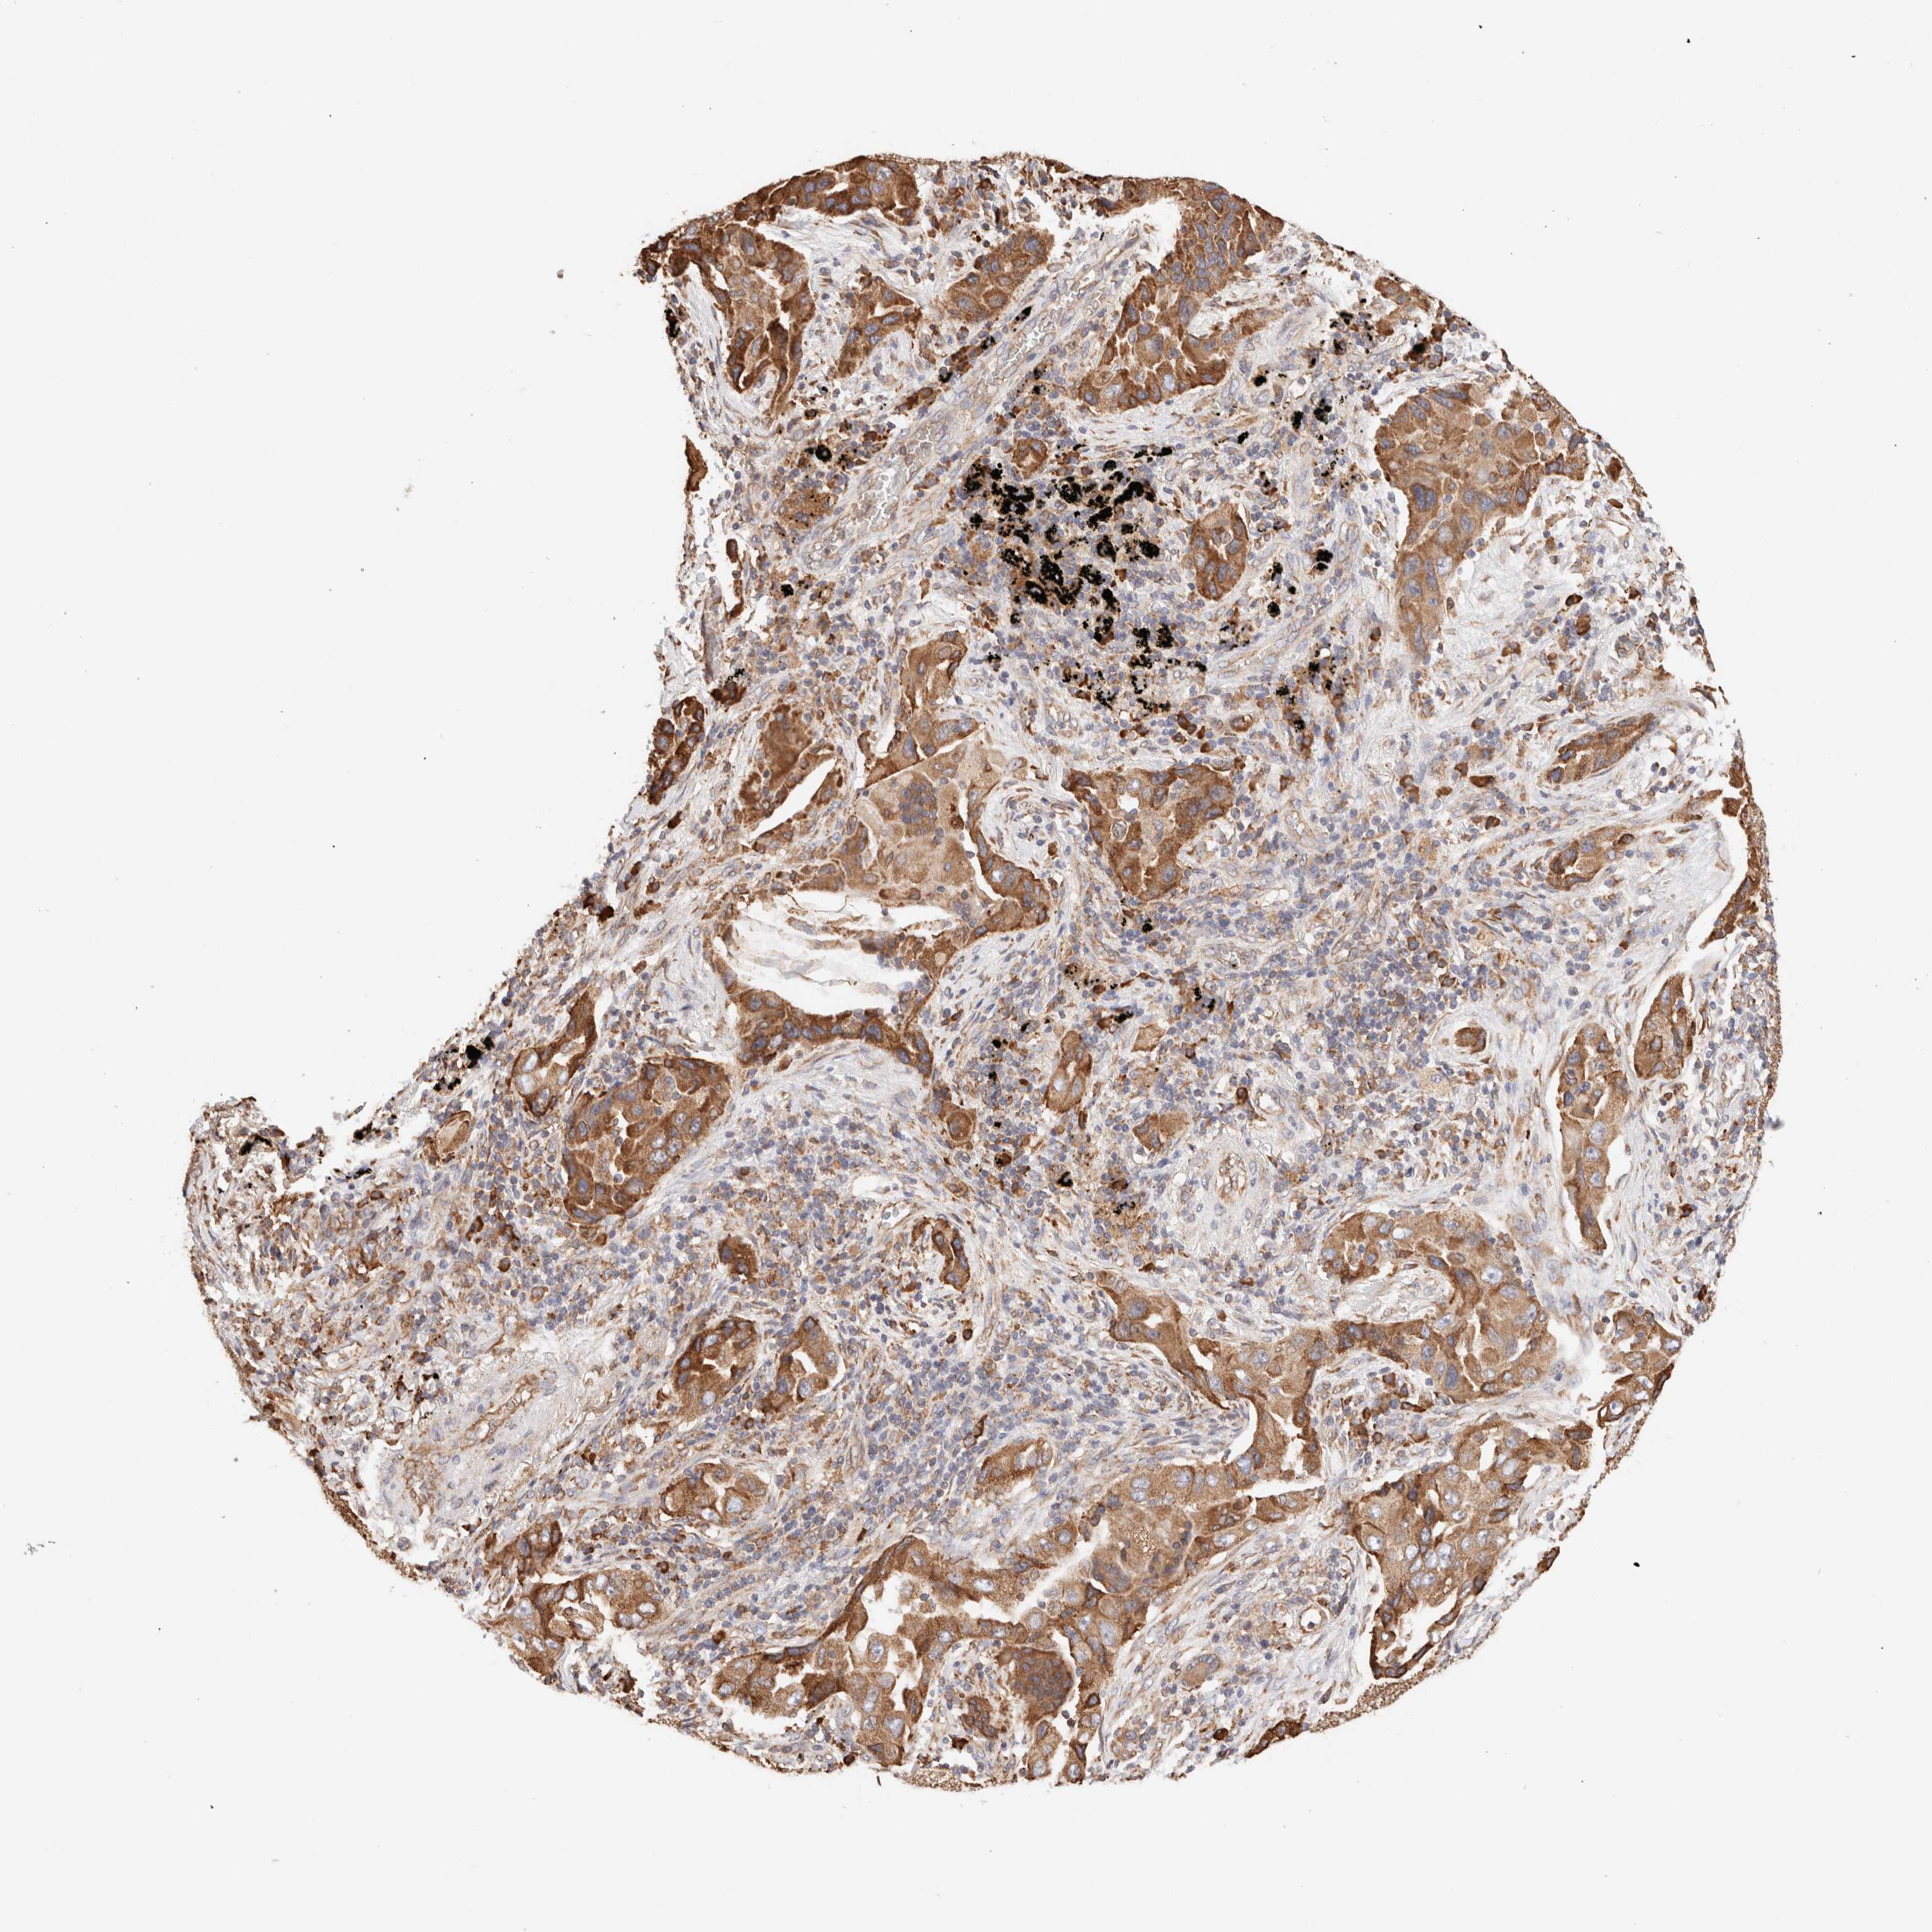

CANCER LUNG CANCER Show tissue menu

LUAD TCGA LUAD VALIDATION LUSC TCGA LUSC VALIDATION PROTEIN LUAD CPTAC PROTEIN LUSC CPTAC PROTEIN EXPRESSION

ANTIBODIES

AND

VALIDATION